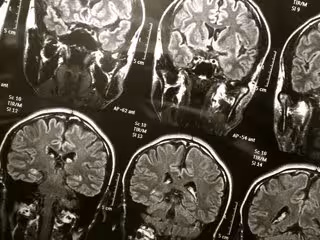

Los grandes espacios llenos de líquido en el cerebro ayudar a identificar a las personas en riesgo de demencia

Cerebro - FLICKR/WYINOUE - Archivo

Las personas con espacios agrandados llenos de líquido en el cerebro alrededor de los vasos sanguíneos pequeños pueden tener más probabilidades de desarrollar problemas cognitivos y demencia con el tiempo, según un nuevo estudio publicado en la edición en línea de 'Neurology', la revista médica de la Academia Americana de Neurología.

Los espacios perivasculares están involucrados en la eliminación de desechos y toxinas del cerebro y pueden estar asociados con los cambios cerebrales asociados con el envejecimiento.

En el estudio participaron 414 personas con una edad promedio de 80 años, que realizaron pruebas cognitivas de las habilidades de pensamiento y memoria y se les evaluó la presencia de demencia al comienzo del estudio y cada dos años durante ocho años. Se sometieron a escáneres cerebrales de resonancia magnética para verificar espacios perivasculares agrandados en dos áreas clave del cerebro al comienzo del estudio y luego cada dos años durante ocho años.